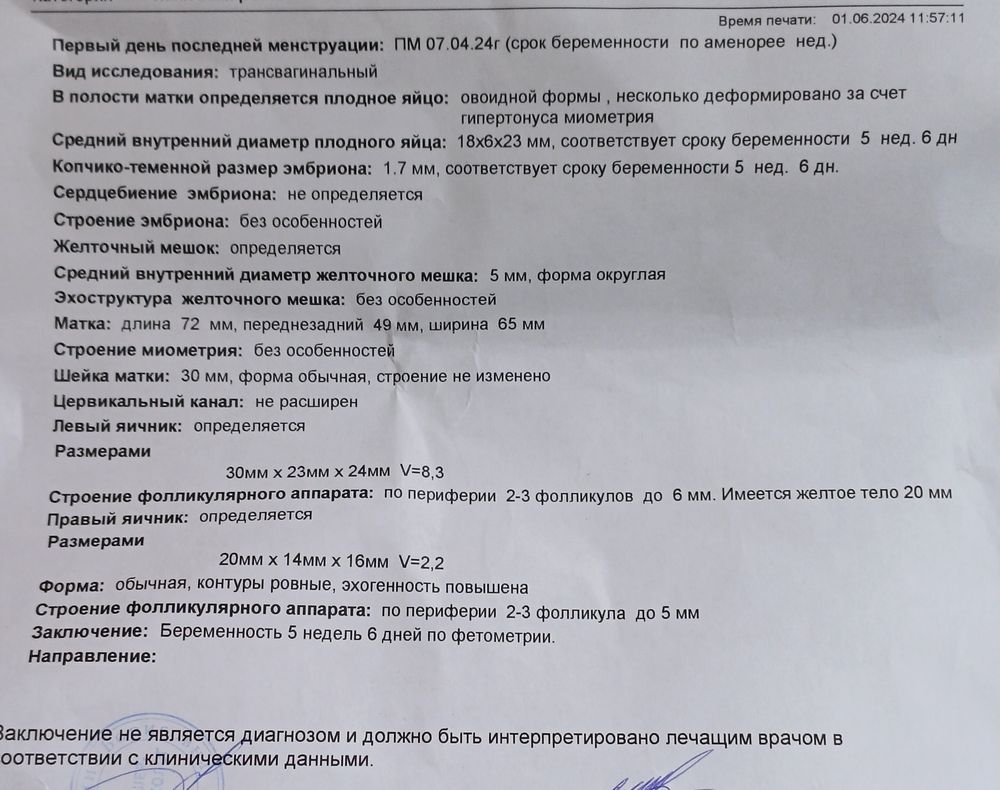

Киньте плз фото вашего УЗИ 5-5,5 недель

УЗИ, КТГ, доплерХочу посмотреть как оно должно "нормально" выглядеть 🙏🏻

Алена, 2 дня назад мне по УЗИ доктор предположил 5 с чем-то недель, фото УЗИ не дал, но мне визуально показалось что желточный мешок большой какой-то. Хочу понять, может так и должно выглядеть